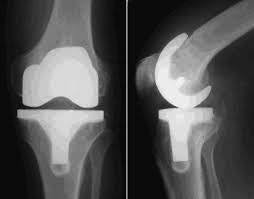

The company ORTHOPEDIC NIKIFOROV was founded in 1998 by the candidate of medical sciences. doctor of orthopedic-traumatologist of the highest category Nikiforov IA Owing to high professionalism and results of work, ORTONIC has gained well-deserved reputation and reputation among colleagues and population of Dnepropetrovsk region and CIS countries (Russia, Moldova, Armenia, etc.). The principle of the enterprise is NO IMPOSSIBLE, it is based on knowledge, experience and active implementation of modern technologies in orthopedics and traumatology. Conservative methods of treatment include individual selection of medicines, therapeutic blockades, manual therapy, massage, physiotherapy (vibration table, magnetotherapy, bioptron, electromyostimulation, etc.), rehabilitation with the suggestion of the necessary concomitant devices and means for the fastest recovery (corsets, bandages, various joint fixators, crutches, walking sticks, etc.). Various minor invasive interventions (chymonucleolysis, vertebroplasty, kyphoplasty, percutaneous nucleoplasty using cold plasma) that are performed on an outpatient basis are successfully used to treat problems associated with spine pathology. The latest modern treatment methods introduced in our company are endoscopic operations using the TYSSES technique of Joimax (Germany) with intervertebral hernias, stenosis and other pathologies of the spine, which allow to avoid complications occurring during open operations and the accompanying general anesthesia. We have many years of successful experience in traditional and modern minimally invasive endoprosthetics of large and small joints, which remains the main direction of our activity. Our company is the exclusive representative of the German company IO International Orthopaedics Holding GmbH, which based on the already known prostheses, its ideas and technological capabilities, has developed and implemented a new concept in hip replacement - an artificial joint prosthesis (ICON). We assist interested colleagues in training the operative technique for installing an artificial joint prosthesis - ICON, both in the workplace and in Germany. For 20 years we have been successfully cooperating with Sanitatshaus Gerd Klinz ortho team, an enterprise that for 20 years has been one of the leading places in Germany for the production of functional prostheses of the upper and lower limbs, as well as cosmetic prostheses of limbs and other body parts (nose, ears, eyeballs, fingers). We have an atmosphere of friendliness and human participation. Politeness, benevolence, the desire to understand and help is the basis of our attitude towards patients. We are always glad to see you and will do our best to make you feel great! We are waiting for you at: Ukraine, Dnepr, Gagarin Ave., 13 (under reconstruction) on all questions to address: tel .: +38 (050) 488-88-92 E-mail: orthonik.ukr@gmail.com Germany, Spine Nano Klinik, Zeppelinstr. 21, Potsdam Tel. +4901801121919 E-mail: kmw.nikiforov@hotmail.de